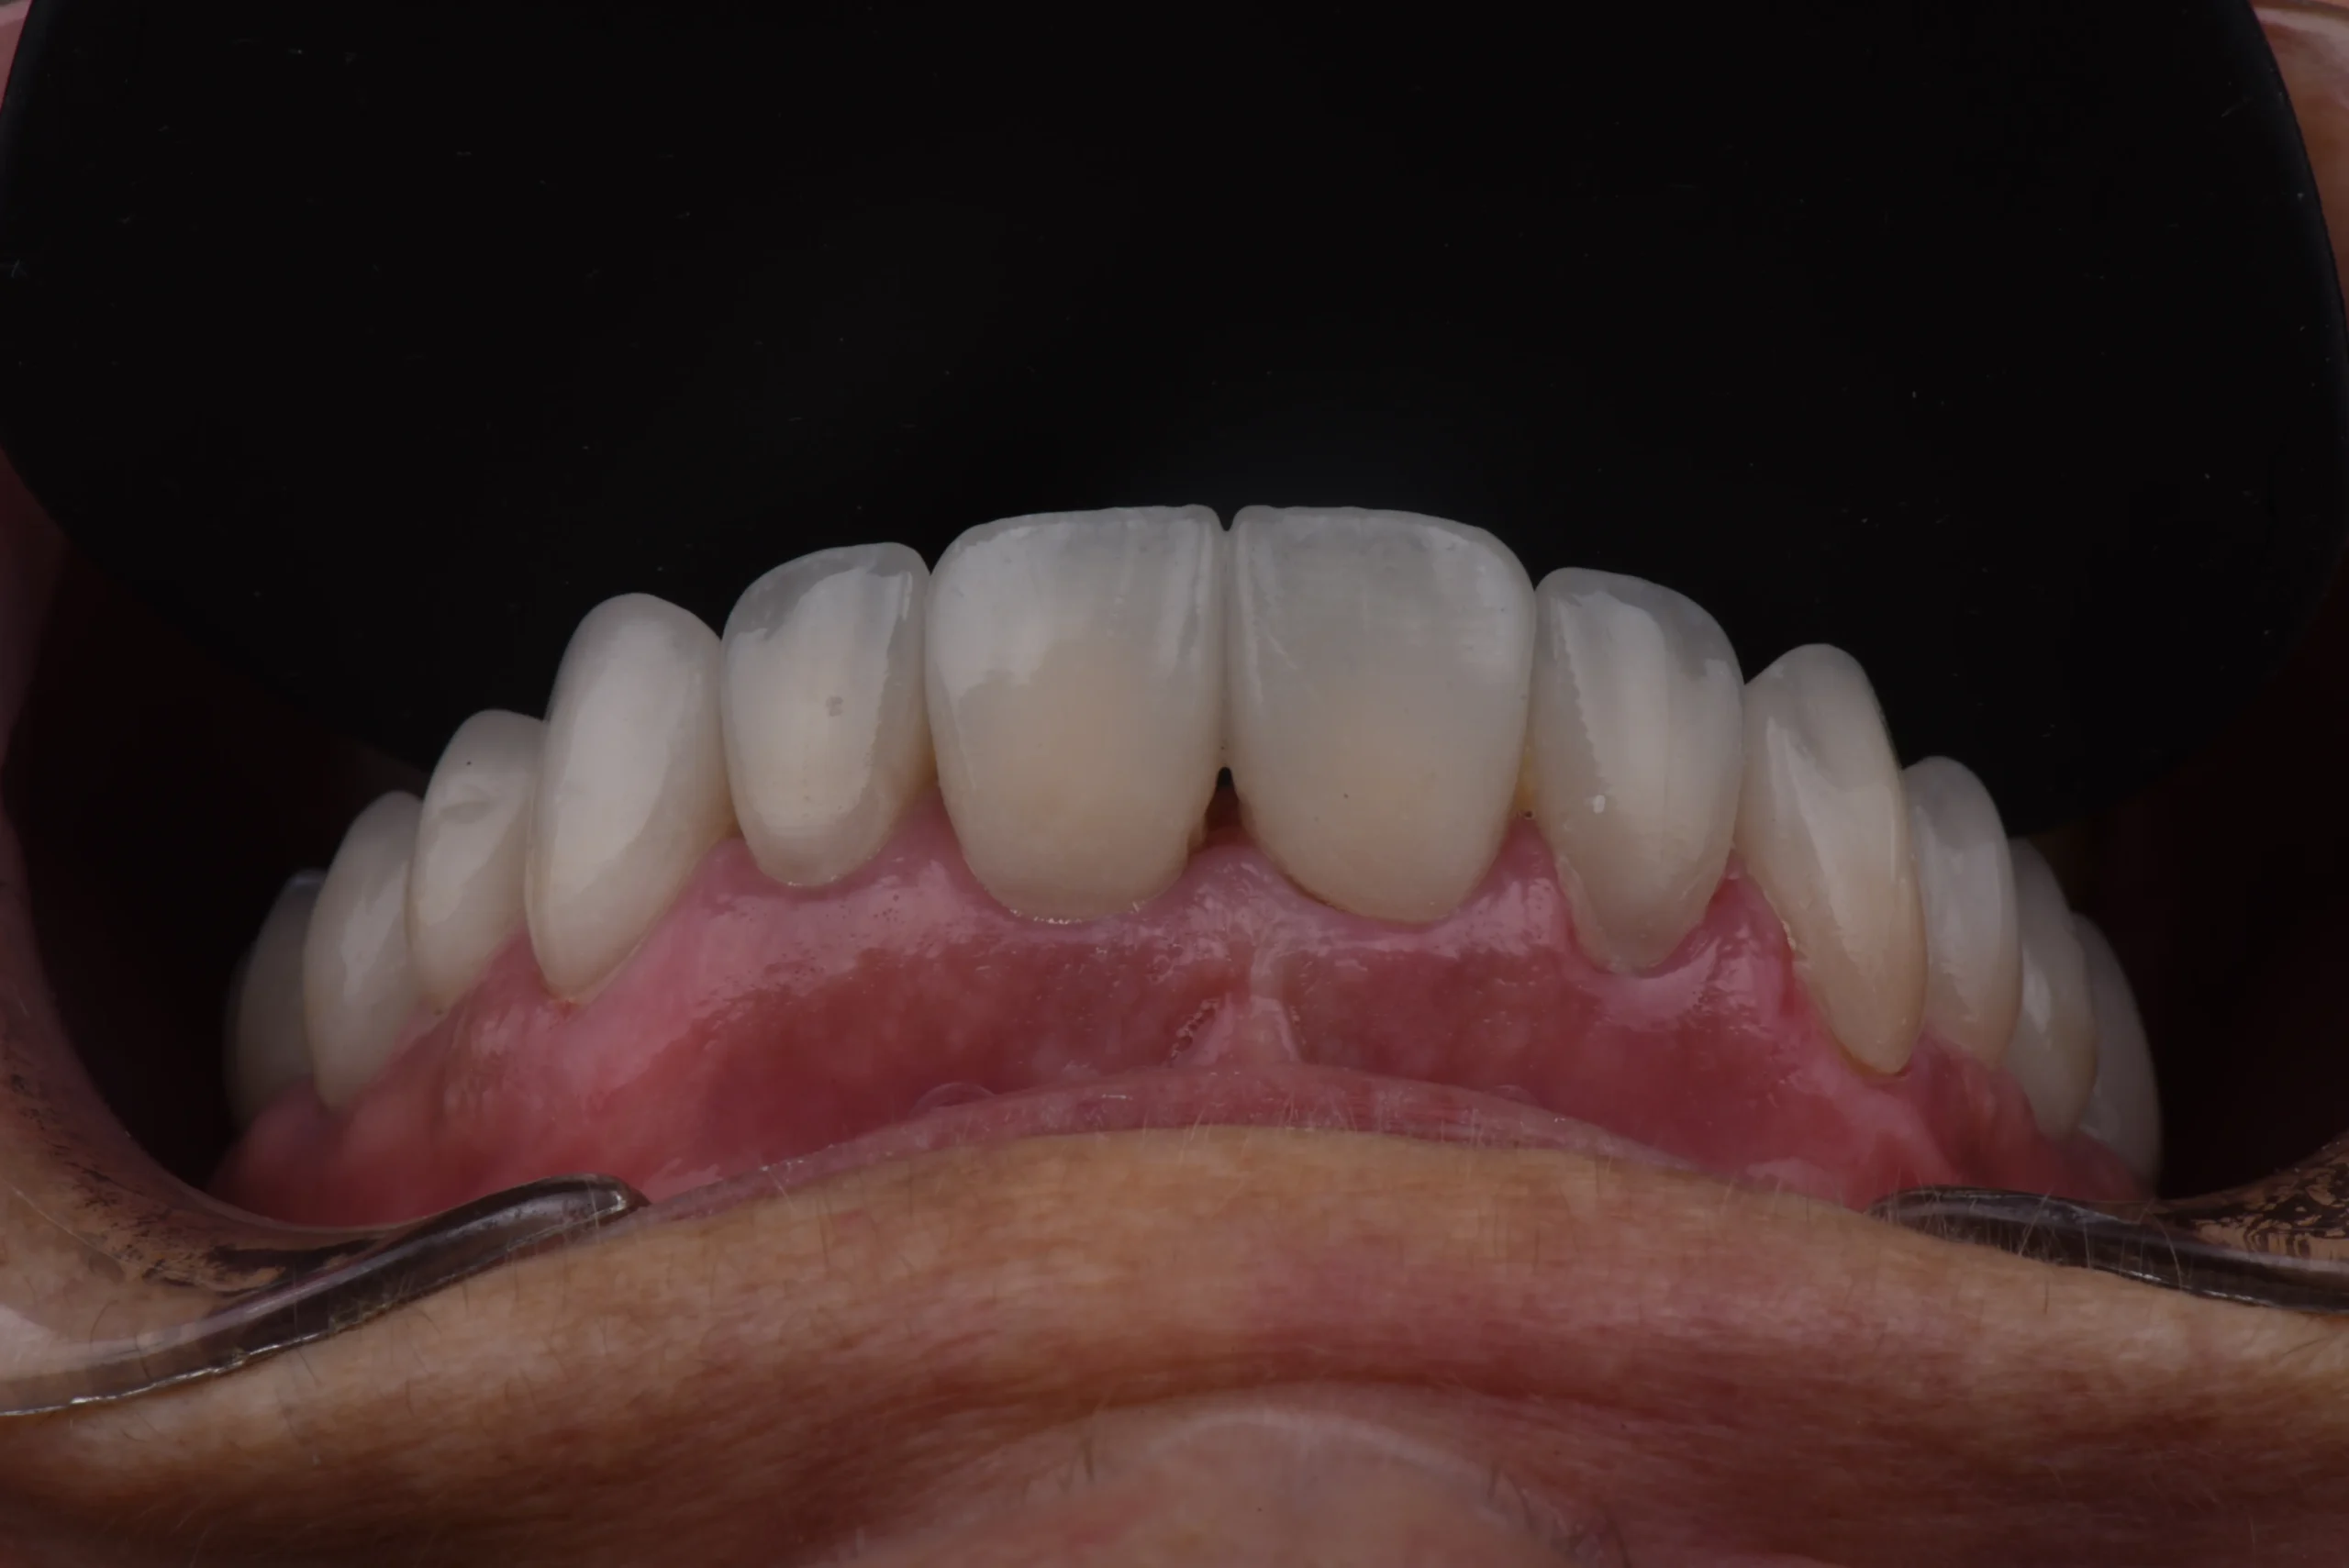

Resultados Resultados

Antes del tratamiento Sorriso depois do tratamento

Recuperacion de salud bucodental, con una sonrisa perfecta y brillante conservando sus piezas dentarias, relizando este tratamiento en tan solo 72horas todo ello gracias a nuestros protocolos digitales.